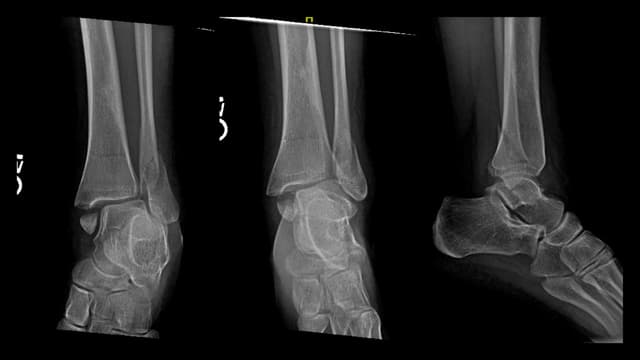

Imaging

Pre-op